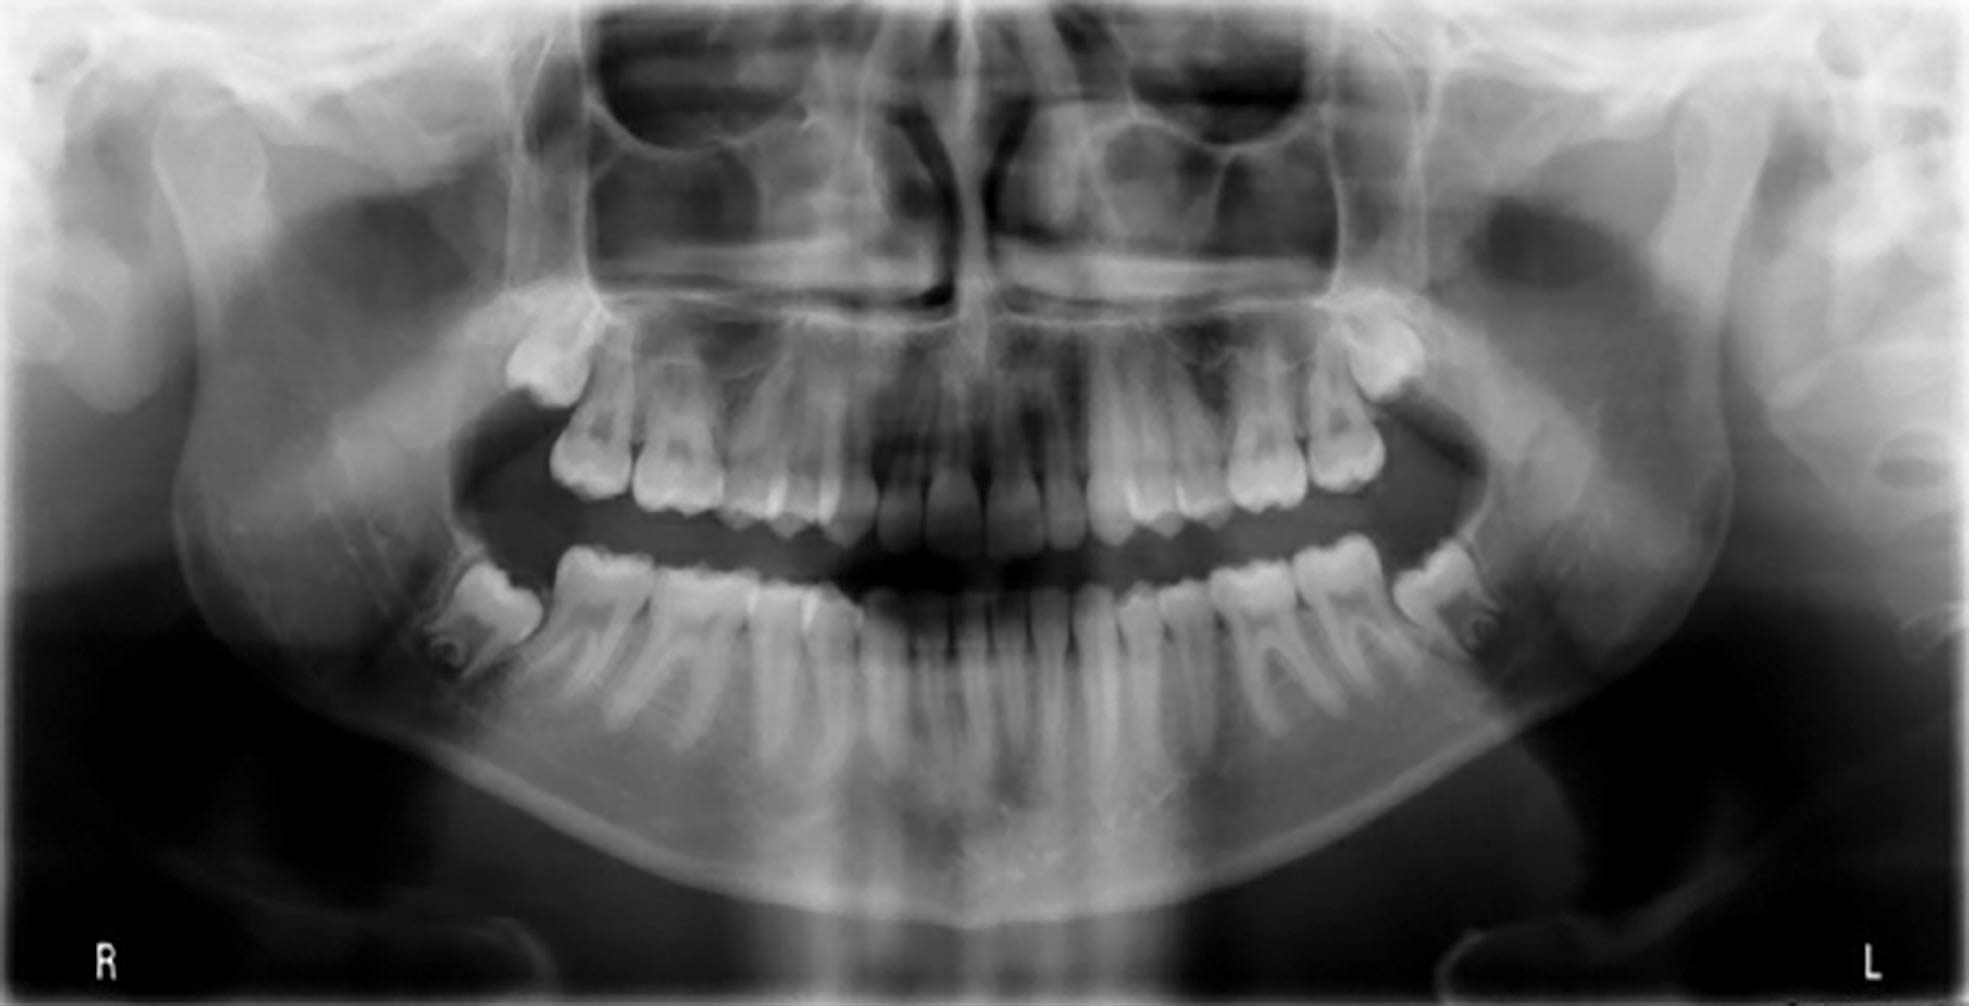

بیمار یک دختر ۱۴ ساله با اکلوژن است. دیپ بایت متوسط تا شدید و کرادینگ متوسط هر دو فک دارد و کانین راست بالا او در کراس است (شکل 68-6 الی 70-6). در این بیمار میخواهیم نحوه اصلاح دیپ بایت و کراس کانین راست بالا را بررسی کنیم.

شکل 68-6

شکل 69-6

شکل 70-6

مرحله اول: قصد داریم که دیپ بایت را با اینتروژن قدامیهای بالا و پایین درمان کنیم. سانترالهای بالا نیاز به اینتروژن مطلق دارند.

نکته: در این بیمار بایت پلیت قرار دادیم تا بتوانیم کانین را از کراس خارج کنیم.

شکل 71-6

نتایج درمان در شکلهای 71-6 و 72-6 مشخص است. هم دیپ بایت شدید و هم کراس کانین درمان شدهاند.کل درمان 16 ماه بود.